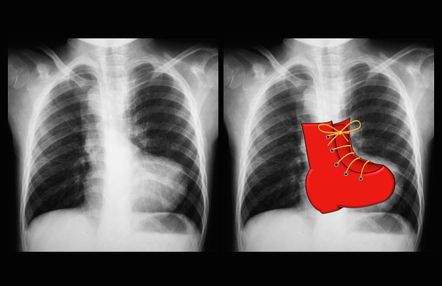

Tetralogy of Fallot is a congenital condition of heart characterized by: 1. Overriding aorta 2. Right ventricular hypertrophy 3. Ventricular septal defect 4. Pulmonary stenosis Right ventricular hypertrophy in tetralogy of Fallot gives heart a characteristic appearance on chest radiograph i.e., boot shaped heart. Reference: https://radiopaedia.org/articles/boot-shaped-heart-2 Image via: https://radiopaedia.org/articles/boot-shaped-heart-2